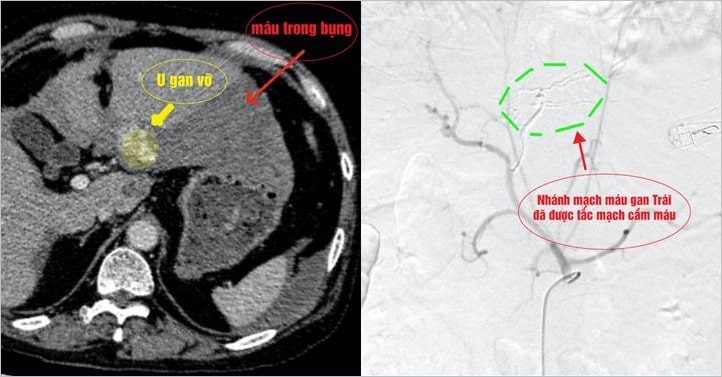

Sau khi thực hiện chụp cắt lớp điện toán đa lát cắt (MSCT) bụng 160 lát, các bác sĩ Ngoại Tổng Quát Bệnh viện Xuyên Á xác định tình trạng mất máu nghiêm trọng là do một khối u trong gan bị vỡ bất thình lình, gây chảy máu xối xả trong ổ bụng.

Hướng giải quyết được đưa ra là sử dụng kỹ thuật can thiệp mạch dưới hệ thống DSA, để tiếp cận và triệt tiêu mạch máu nuôi u gan bị vỡ. Do tình trạng cần can thiệp tối khẩn, tất cả các êkip bác sĩ, điều dưỡng, kỹ thuật viên, từ nhiều đơn vị: chăm sóc tích cực, gây mê, can thiệp nội mạch được huy động cùng cứu sống bệnh nhân.

Trong 30 phút, ống thông được luồn từ động mạch đùi của bệnh nhân đã tiếp cận được nhánh mạch máu gan trái đang xuất huyết liên tục. Êkip mổ dùng kỹ thuật nút mạch, kiểm soát được tình trạng mất máu. Các dấu hiệu sinh tồn như mạch và huyết áp được cải thiện.